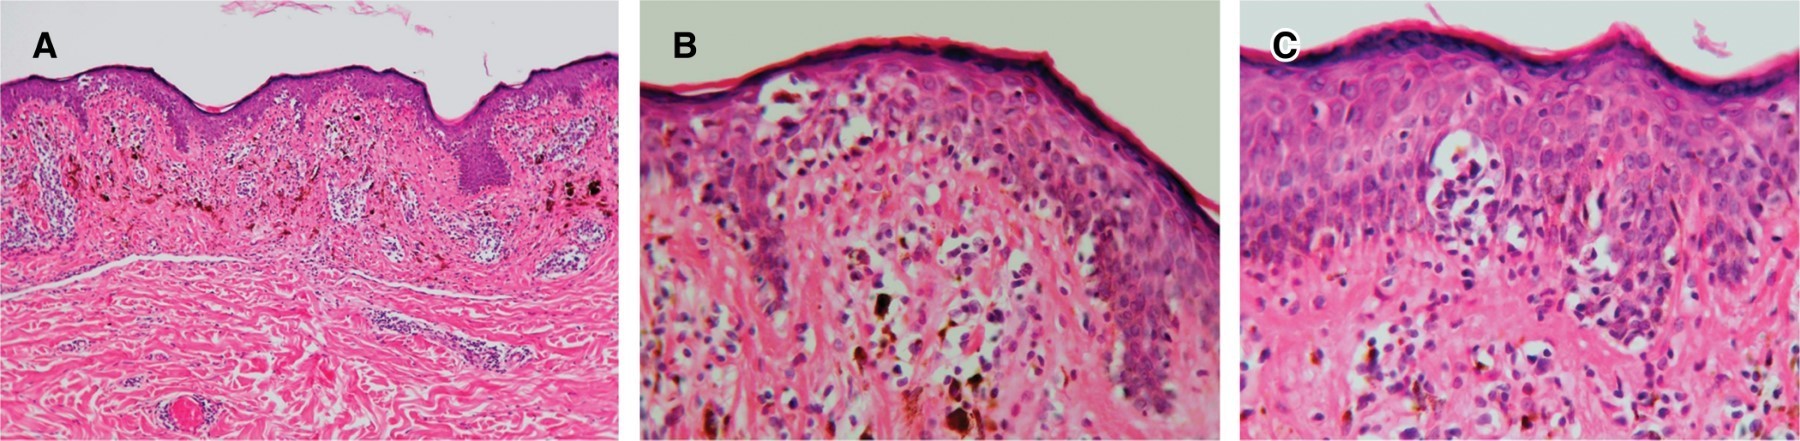

En cuanto a los hallazgos histopatológicos de los 27 pacientes, 24 (89%) mostraron epidermotropismo, 22 (81%) linfocitos perivasculares, 22 (81%) caída del pigmento, 14 (52%) hiperpigmentación de la capa basal, 15 (56%) degeneración hidrópica de la capa basal, 11 (41%) linfocitos atípicos, siete (26%) microabscesos de Pautrier, tres (11%) invasión folicular y tres (11%) melanófagos (Figura 2 y Tabla 3).

En las dos últimas décadas se han propuesto diversos criterios citológicos e histopatológicos para identificar las categorías: "diagnóstico de", "consistente con" y "sugestivo de" MF, por lo que la Sociedad Americana de Dermatopatología con la contribución de la Academia Americana de Dermatología y el Colegio Americano de Patólogos en el año 2018 desarrollaron el "Uso Apropiado de Criterios en dermatopatología para enfermedades linfoproliferativas".16,17,21 De acuerdo con esta clasificación, los resultados histopatológicos fueron reportados como compatibles con MF ocho (30%) de los casos, concluyentes 14 (52%) y en cinco pacientes se integró el diagnóstico por correlación clínico-histopatológica, cayendo en la categoría "sugestivo de". En el estudio histopatológico en un caso se reportó folículotropismo, y en los cinco casos arriba señalados, la presencia de linfocitos perivasculares. A nivel histopatológico, además de las características adicionales de la MF clásica, se han descrito la degeneración hidrópica de la capa basal simulando "dermatitis de la interfase" y la presencia de melanófagos en la mayoría de los casos. En relación con la inmunohistoquimica, la mayor parte de pacientes con MF hiperpigmentada muestran fenotipo CD8+. Se cree que estos linfocitos T citotóxicos pueden afectar a los melanocitos o queratinocitos basales, resultando en cambios de la interfase e incontinencia del pigmento melánico, lo cual se manifiesta clínicamente como hiperpigmentación.12 En nuestro estudio, en 22 pacientes (81%) se demostró la presencia de caída del pigmento, en 14 (52%) hiperpigmentación de la capa basal, en 15 (56%) degeneración hidrópica de la capa basal y en tres (11%) melanófagos, hallazgos consistentes con la manifestación clínica.

En las dos series de MF hiperpigmentada de Israel y Suiza,12,18 los hallazgos histopatológicos en los tres casos de Israel fueron similares, con epidermotropismo de células individuales y discretos infiltrados perivasculares de pequeños linfocitos, así como marcada incontinencia del pigmento. En todos los casos de Suiza se observó dermatitis de interfase con melanófagos, además de epidermotropismo e infiltrado linfocitario dérmico.